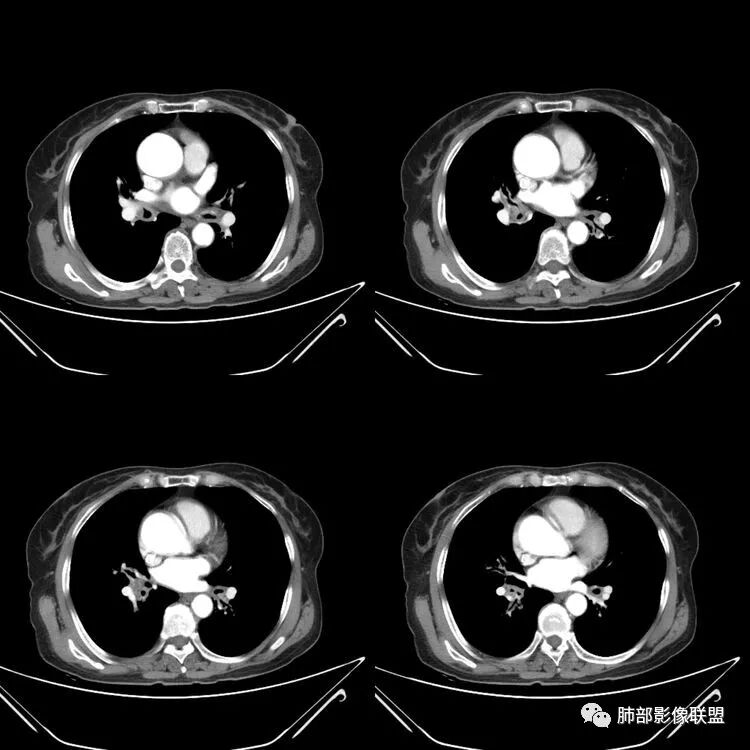

患者,女,64岁,反复咳嗽、咳痰、胸闷10年,加重2周患者10余年来每当受凉感冒出现咳嗽、咳痰、胸闷,有时痰中带血,输液治疗(具体不详)可好转。既往有声带肥厚手术病史。CT示气管、主支气管及分支支气管管壁弥漫性增厚累及膜部,局部伴钙化,管腔狭窄,考虑淀粉样变性

患者,女,64岁,反复咳嗽、咳痰、胸闷10年,加重2周。气管支气管及两肺下叶 支气管弥漫性的环状增厚,管腔扩张,管腔感觉比较松弛。第一感觉,气管支气管淀粉样变。鉴别诊断,1、支气管内膜结核,肺内散在一些支气管的播散病灶,粟粒结节为主,形态比较单一。2、复发性的多软骨炎,就得了解一下其他部位,有没有多个部位的软骨炎。这个病人右侧胸廓缩小,升主动脉明显的扩张,其横径明显的超过了降主动脉。

南边:肺部有肺气肿支气管腔狭窄淀粉样变性?复发性多软骨炎?血管炎?慢支?结核?曲霉菌?南边:一般还是淀粉样变性与复发性多软骨炎鉴别其次就是支气管骨化症,但是骨化下朝上,且壁结节状钙化明显,本例不太支持。至于结核、曲霉菌?1.结核,一般不会这么广泛,支气管壁狭窄后扩张2.曲霉菌可以这么广泛,但是支气管壁管腔扩张,而且附近脂肪间隙有炎性反应,不太支持;3.血管炎,一般合并肺内有病灶,但是声带受累,放待排;4.软骨炎一般全身受累,例如耳廓等;而且膜部不受累,不太支持;倾向于淀粉样变性;淀粉分很多型,气管支气管是最常见的。尘缘:影像上生理性钙化与支气管骨化无法区别,镜检也不好鉴别,需要依赖活检,看粘膜中是否合并炎性改变(淋巴细胞,组织细胞等炎性细胞侵润)来鉴别Coke with ice:经常看到的这种是老年性肺改变,又称年龄相关肺改变。气管和支气管弥漫性软骨钙化,常见老年女性。尘缘:支气管骨化症很罕见的,所以绝大多数还是生理性钙化。对于老年人,无临床症状的钙化,还是基本上都是生理性钙化,无临床意义。大雄:如果管壁钙化伴明显增厚 影像还是提示一下建议支气管镜稳妥些

三、影像表现

1.气管支气管型

①气管支气管壁增厚,形成粘膜下斑块与结节

②管腔广泛狭窄、闭塞

③管壁钙化

④膜部受累(具有重要鉴别意义)